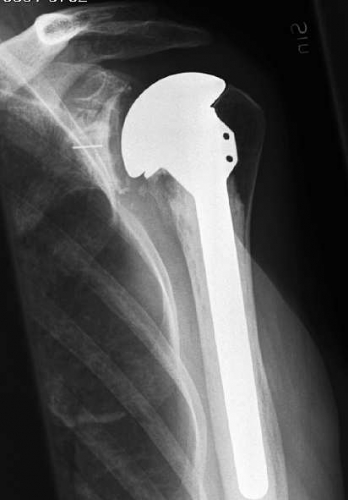

Total axelartroplastik (Figur 4) blev successivt allt vanligare sedan Neer konstruerat sin polyetylenglenoid och rapporterat goda uppföljningsresultat [11]. God smärtstillning och förbättrad funktion konstaterades i ett flertal andra studier. Lossningsfrekvensen på humerussidan är mycket låg om protesen cementeras som Neer ursprungligen beskrev. Vid ocementerad press fit-fixation av humeruskomponenten med samtidig cementfixation av glenoiden har ökad röntgenologisk lossningsfrekvens av stammen påvisats i långtidsstudier, men kliniskt är lossning inget stort bekymmer.